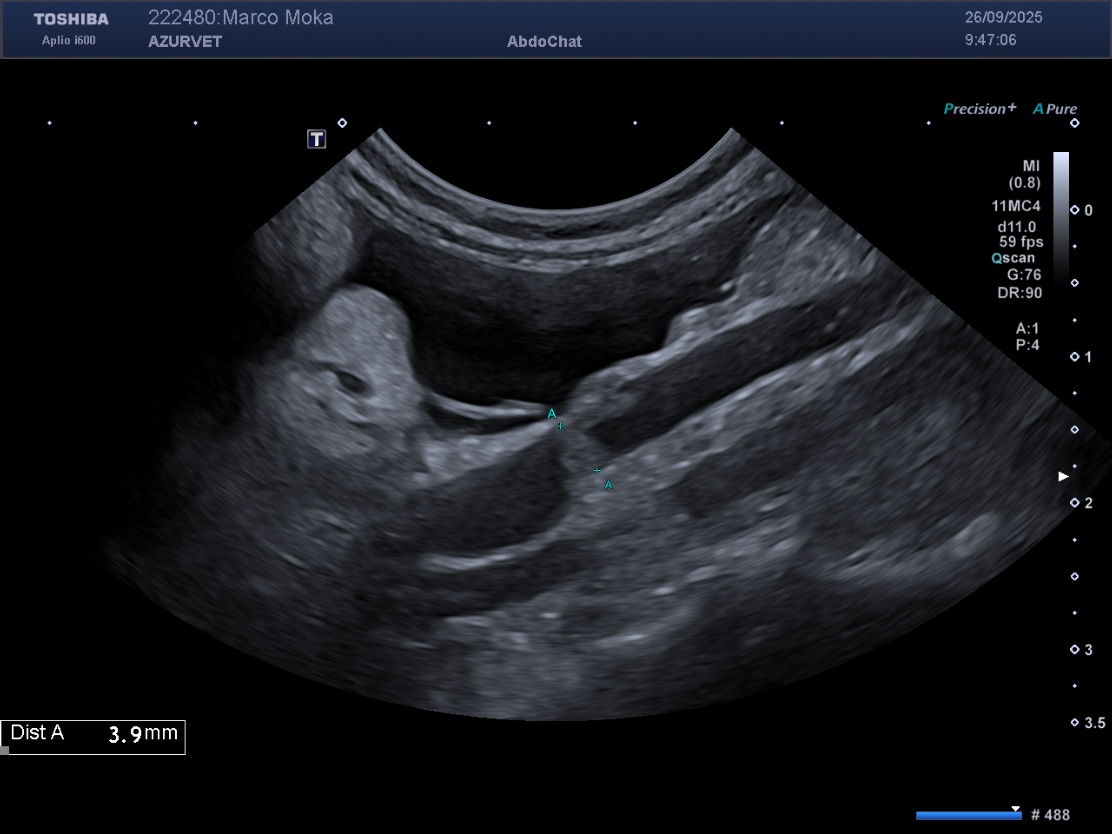

1) Un épaississement de la paroi de la vésicule biliaire lié à un oedème pariétal (secondaire à l'hypoalbuminémie) : figure 2 ci dessous.

Figure 2 : épaississement pariétal discret de la paroi de la VB chez le même animal que la figure 1.